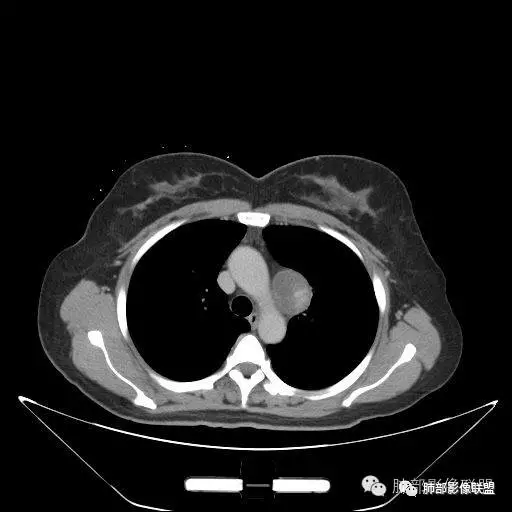

大雄:定位: 纵隔(往左推移气管 往前推移腔静脉 往下推移肺尖胸膜)定性: 良性(边缘光滑,与周围结构境界清晰,无侵袭性生长特点)特征:增强可见AB区(富细胞区与粘液区),延迟强化明显。考虑:神经鞘瘤 ,鉴别:SFTKing:纵隔偏良性肿瘤,与甲状腺无关。首先考虑神经鞘,其他如副节,SFT,巨淋巴待鉴别。飞鹰行动:右侧上胸腔近纵膈类圆形软组织占位,边界清晰光滑,内见囊变,增强渐进性强化,考虑来源纵膈的病变,神经鞘瘤可能,鉴别孤立性纤维瘤。小兜:右上纵隔椭圆形占位,胸膜掀起,肺组织受压,气管受压移位,考虑来源于纵隔,边缘光滑,增强扫描渐进性不均匀强化,内见大片无强化区,考虑为神经鞘瘤可能,鉴别SFT。陈学君:后纵隔占位,多发囊变,渐进強化,考虑鞘瘤,鉴别SFT红星:右上胸廓入口类圆形肿块,肺瘤界面清晰,肺支气管及血管受压,强化不均,片状楔形坏死,考虑来源纵隔占位,神经鞘瘤。鉴别STF、肉瘤?宇宙:右上后纵隔旁椭圆形肿块,边缘光整,向上突入颈根部,肺组织、血管及气管受压移位,密度不均匀,不均匀渐进强化,囊变,考虑神经鞘瘤,鉴别SFT

Kery Wang:

右侧上胸腔近纵膈类圆形软组织占位,边界清晰光滑,考虑来源纵膈的病变,神经源性可能,鉴别孤立性纤维瘤。医然为伱つ:有AB区,首先考虑鞘瘤,鉴别SFT

1. 右上胸廓入口区类椭圆形块影,边界清楚光整,纵向“嵌顿”于颈根部及上纵隔,向上推移右锁骨下动静脉,向外下方推移上肺胸膜及肺组织(肺血管、支气管),向前推移上腔静脉,界限清楚。

2. 块影不均匀轻度强化,可见较均匀实性区及液性密度区,未见积气、囊壁样结构、钙化或脂肪密度。可疑部分肋间动脉分支进入。

1.块影定位肺外-上纵隔。块影密度以及强化方式不支持胸腔内甲状腺肿、副节瘤、巨淋巴结增生、支气管囊肿以及畸胎瘤等。

肿块部位、密度以及强化特点聚焦于良性神经鞘瘤及孤立性纤维瘤。

2.肿块远离胸膜向上延伸不大符合胸膜来源的孤立性纤维瘤。

3.而“A/B”区密度特点以及上下径较大更支持神经鞘瘤,尽管这不属于好发部位。